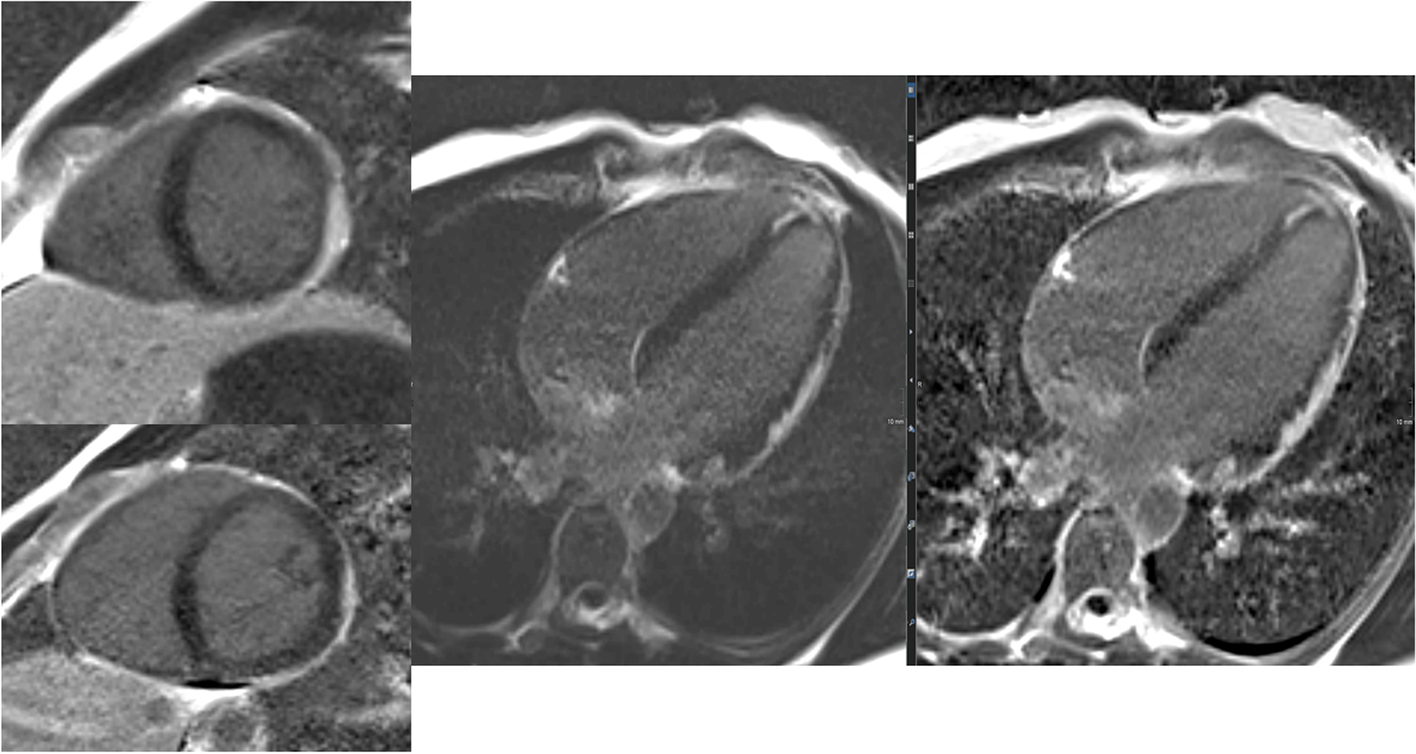

The basic components of cardiac MRI protocols are cinematographic imaging (CINE), 2D flow and late gadolinium enhancement (LGE), and 2D/3D flow. Extended protocols also include 4D flow and mapping.

Figure 5 summarizes integral parts of the LV and RV analyses.

Fig. 5

(Functional imaging): assessment of cinematographic (“CINE”) images allows a rapid overview of global and regional functions comparable to echocardiography. Standard are planned projections in the long- and short-heart axis. Here, images of a 12-year-old girl with follow-up after multisystem inflammatory syndrome in children (PIMS) are presented: a 4-chamber view in diastole (left upper row) and systole (left lower row) and a 2-chamber view also in diastole (middle) and systole (right)